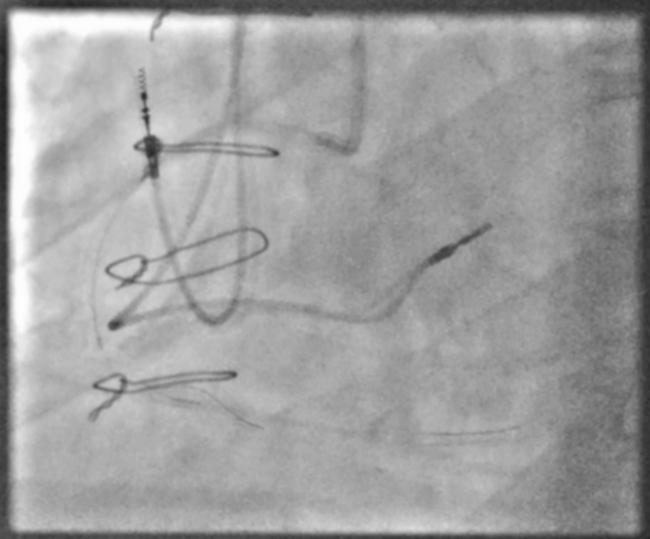

Application of the hybrid algorithm for the treatment of coronary chronic total occlusions requires the operator to readily deploy complex techniques and advanced technologies to achieve successful revascularization. Patient-specific factors and limitations in torquability and material strength of low-profile equipment such as microcatheters can result in procedural complications due to device fracture. Using a mini-series of 2 cases to demonstrate the successful application of antegrade dissection re-entry techniques to overcome such challenges, we highlight procedural complexities and risk, and review prior approaches and literature.